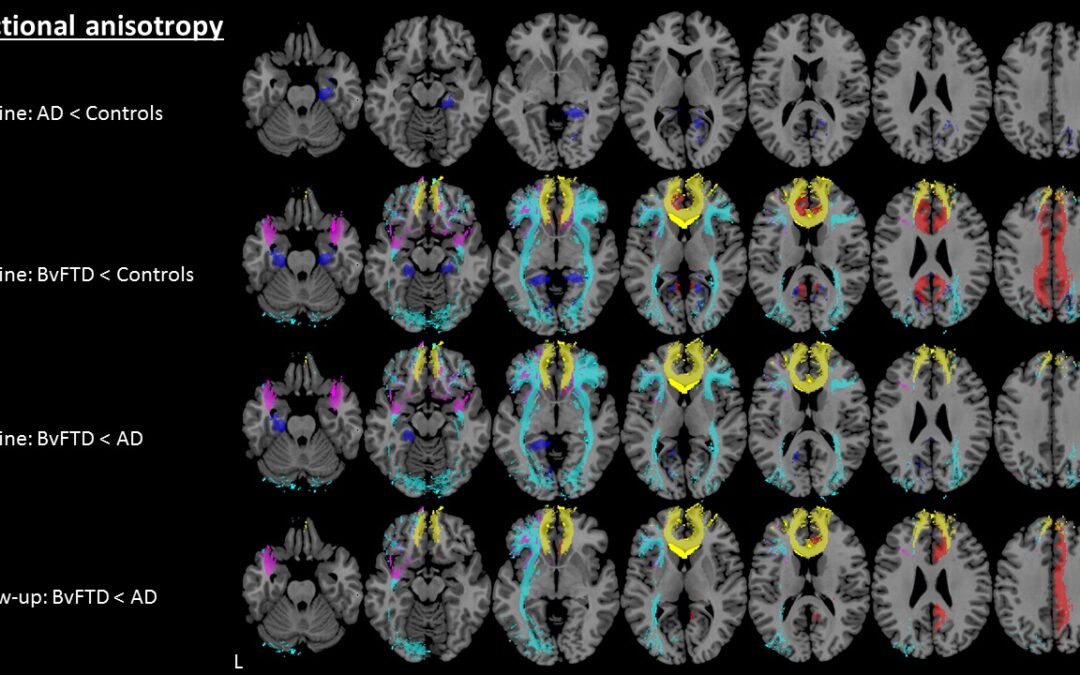

Article: Exploring quantitative group-wise differentiation of Alzheimer’s disease and behavioural variant frontotemporal dementia using tract-specific microstructural white matter and functional connectivity measures at multiple time points